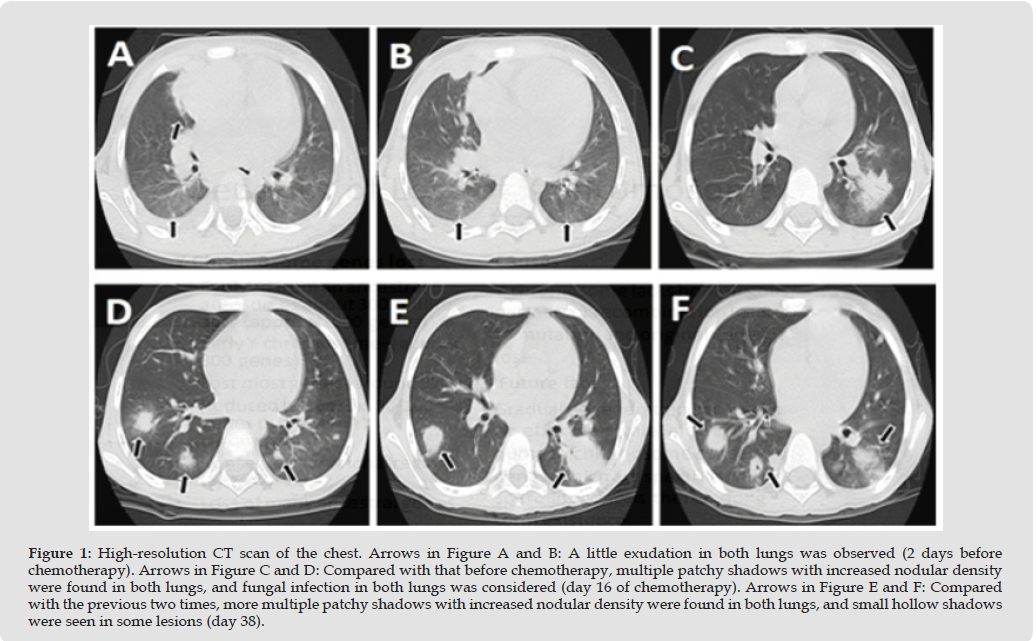

A 7-year-old female child was admitted to our department due to “fatigue and pale face”. The patient’s blood routine examination was initially performed at the local hospital: the white blood cell count was 215 × 109/L (4–10 ×109/L), the hemoglobin level was 29 g/L (110–150 g /L), and the platelet count was 22 × 109/L (100–300 × 109/L). After admission to our department, the bone marrow was extracted and sent for morphological, immunological, cellular, and molecular genetics (MICM) typing of bone marrow cells. The diagnosis was ETP-ALL (HOX11 positive). The chest CT scan showed a little exudation in both lungs (Figures 1A & 1B). Relevant organ function was evaluated, revealing no contraindications. The chemotherapy was started according to the remission induction regimen of ALL (dexamethasone + vincristine + daunorubicin + pegaspargase). Agranulocytosis in the child was observed on day 8 of chemotherapy. On day 13, the child had a fever, with a peak temperature of 39.0°C. The lesion location was not clear. The monitored CRP was between 89 mg/L and >200 mg/L (0–10 mg /L), and the GM test was 1.141– 4.467 (positive). On day 16, a chest CT scan showed multiple patchy shadows with increased nodular density in both lungs, and fungal infection in both lungs was considered (Figures 1C & 1D).

After the aforementioned positive systemic and local treatment, the digestive tract symptoms and anemia of the child improved and diarrhea stopped, but the fever continued for more than a month and the daily heat peak fluctuated between 37.0 and 39.6℃. The number of systemic skin lesions increased. Some skin lesions gradually collapsed and appeared crater-like, and a small part of the skin lesions fell off and tended to heal (Figure 2F). The skin rash on the face was exfoliated, and the wound was formed. However, the newly added soft tissue mass spread to the deep part of the limbs in the later period. The re-examination of bone marrow (day 36) showed active bone marrow hyperplasia, with prolymphocytes accounting for 1.5%. The re-examination of chest CT (day 38, as shown in Figure 1E & 1F) indicated an increased number of lesions and small voids in some lesions. The blood routine examination before discharge revealed the following: The white blood cell count was 7.3 × 109/L, the hemoglobin level was 86 g/L, the platelet count was 139 × 109/L, the absolute lymphocyte count was 0.67 × 109/L, the absolute neutrophil count was 6.23 × 109/L, and the CRP level was 114.1 mg/L. The family could not pay the long-term medical expenses.

The imaging manifestations of pulmonary Fusarium infection included vascular infiltration. Nodules or masses found by chest CT were the most common, and 80% of patients had no halo sign [6]. Sassi et al. showed that invasive Fusarium infection was suspected if chest CT showed lung infiltration with low-density signs but no halo sign or signs of occluded vessels [7]. In the present case, severe systemic diffuse invasive Fusarium infection occurred in the bone marrow suppression stage after chemotherapy, involving the lung, skin, and digestive tract. The clinical manifestations of the child were recurrent moderate and high fever, with mild respiratory manifestations, accompanied by a little cough, mainly wet cough. A total of three chest high-resolution CT examinations were performed, and multiple patchy shadows with increased nodular density appeared in the last 2 times, indicating fungal infection. Later, bronchoscopy alveolar lavage, smear, culture, and metagenomic examination of the alveolar lavage fluid did not detect fungi, which might be related to the use of antifungal drugs for a long time.